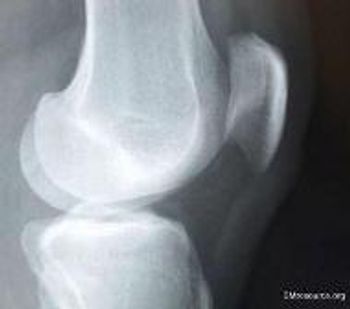

While demonstrating his retro dance moves, a 31-year-old injures his knee doing “the Twist.” Now he can barely walk. Would you order an x-ray?

An occult fracture in the knee is most often a nondisplaced lateral tibial plateau fracture.